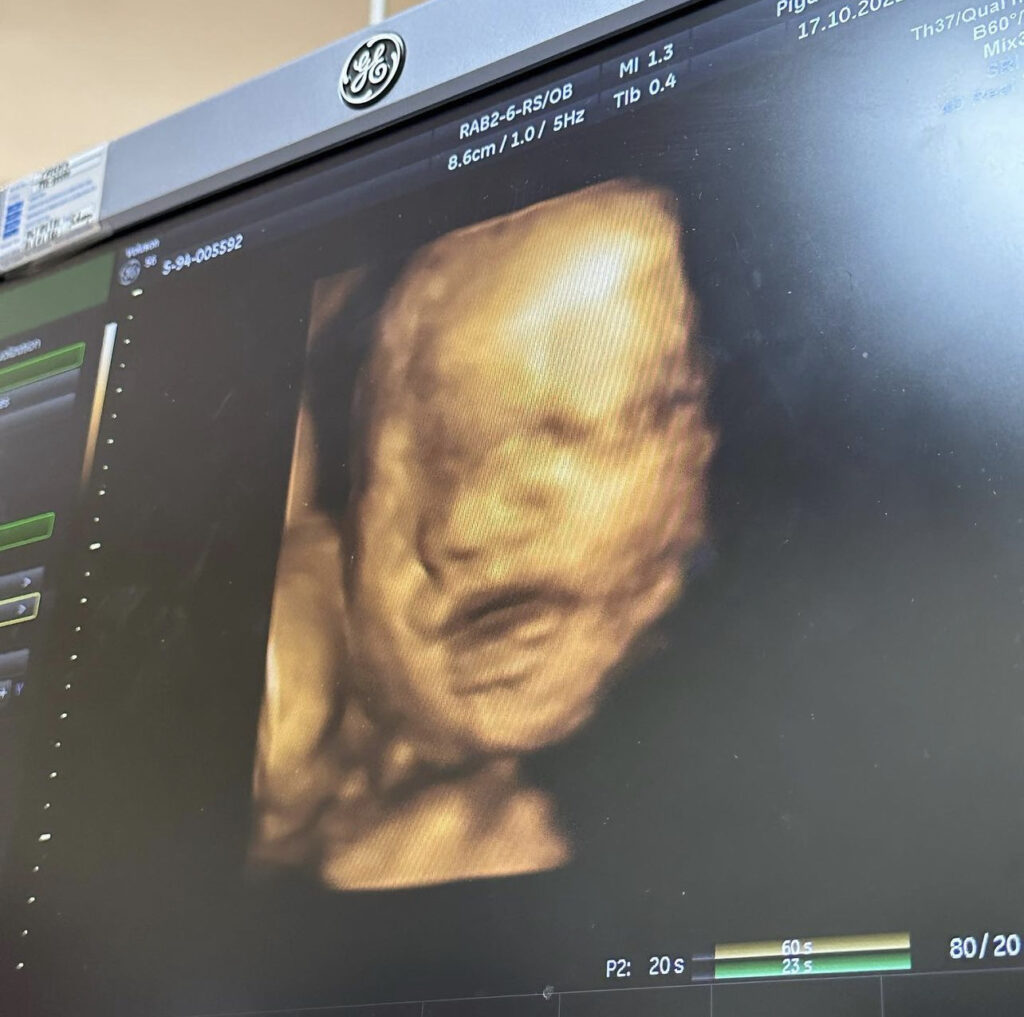

ล่าสุดสาวบุ๋ม ได้ออกมาโพสต์ภาพอัลตร้าซาวด์หน้าลูกชายครั้งแรก ให้แฟนคลับได้ยลโฉมกัน ต้องบอกเลยว่าหน้าอวบอิ่ม จมูกพุ่ง หล่อแต่ไกลมากเลยค่ะ มาพร้อมแคปชั่นว่า”หน้าเหมือนใคร??“ ซึ่งงานนี้แฟนคลับและคนในวงการบันเทิงต่างเข้ามาแสดงความยินดีกับสาวบุ๋มกันสนั่นไอจี